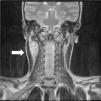

Niña de 13 años con tumoración cervical derecha detectada por la paciente desde hace unos 3 meses. A la palpación, bultoma de 3×4cm, de consistencia dura, adherido a planos profundos, sin inflamación ni dolor. No hay antecedente de proceso infeccioso, fiebre o síntomas constitucionales. La analítica sanguínea y la radiografía de tórax fueron normales. En la ecografía cervical se evidenció una masa en el espacio carotídeo derecho, de 4×2×4cm, de forma ovoidea, bien delimitada, isoecoica al músculo y con abundante vascularización en su interior. Estos hallazgos hicieron sospechar una tumoración de origen neural. Se completó el estudio con una resonancia magnética cervical. Las imágenes obtenidas (figs. 1 y 2) confirmaron como primera opción la sospecha de un schwannoma del vago, dada la morfología fusiforme de la lesión, con eje mayor longitudinal siguiendo el trayecto del nervio (fig. 3). Se realizó resección completa de la tumoración dependiente de la rama nerviosa cervical. El estudio histológico confirmó el diagnóstico de schwannoma del nervio vago. La paciente presentó síndrome de Horner derecho posquirúrgico sin otras complicaciones. Tras 6 meses no existe evidencia de recidiva tumoral.

Los schwannomas del cuello se presentan como masas de crecimiento lento, benignas, inicialmente sin clínica neurológica. Resulta característica su movilidad en sentido lateral, pero no en la dirección del eje nervioso1. Son más frecuentes entre la tercera y sexta década de la vida, habiendo casos descritos en niños2. El diagnóstico se basa en la sospecha clínica y pruebas de imagen; la PAAF presenta escasa rentabilidad. La resección quirúrgica aporta unos excelentes resultados3, sin apreciarse recidiva tumoral.